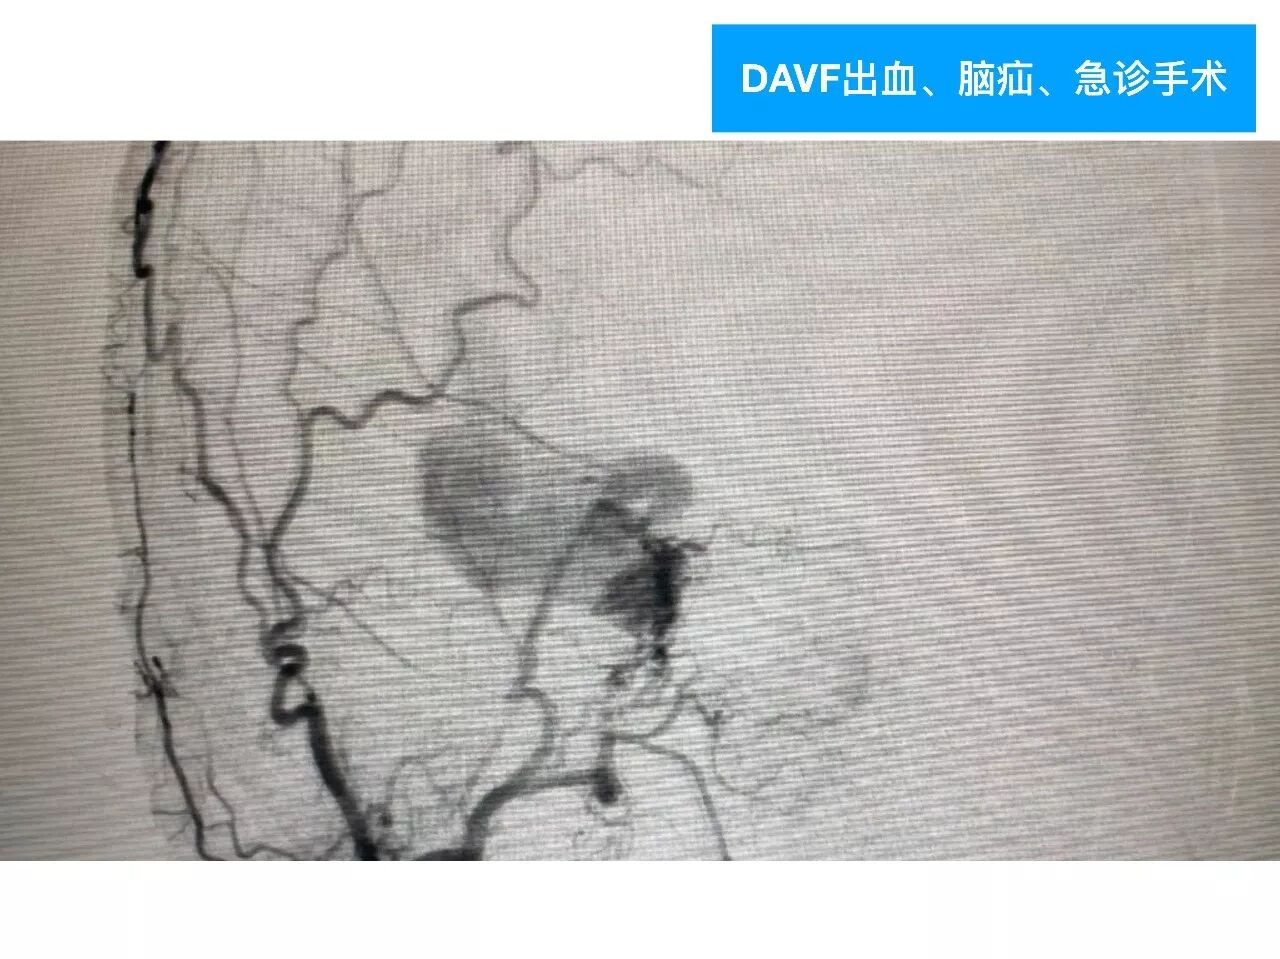

今天为大家分享的是《颅脑创伤-神经重症病例周刊》第四十九期,由天津市环湖医院神经外科五病区主任佟小光教授团队带来的:DAVF出血、脑疝急诊手术一例,欢迎阅读。

(3)对于此类DAVF,主要是蝶顶窦与海绵窦之间的逆流;扩大的中颅底入路,先闭塞引流入海绵窦的颈外动脉颌内动脉分支;然后将一侧海绵窦所有的漏口夹闭,切断所有的脑静脉与海绵窦逆流;

(4)虽然没有处理颈内动脉-海绵窦漏,在漏口闭塞后,所有的漏几乎都消失了。